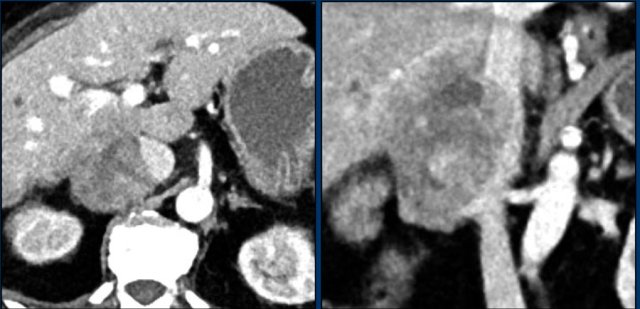

Axial and coronal CT images in a patients with a right adrenal carcinoma and extensive IVC invasion.

The coronal image also shows tumor extension into the right renal vein.

Axial and coronal CT images of another patient with an adrenal carcinoma with extensive IVC invasion (yellow arrow).

IVC and renal vein tumor invasion are seen in up to 20% of patients.